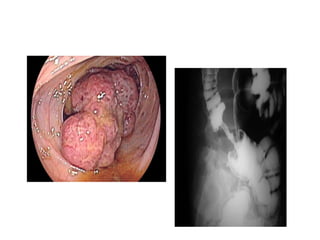

Tumors

❖usually associated with chronic anemia

❖ can also present ulcerative lesions that bleed

persistently

❖ endoscopic therapy is often successful in

controlling hemorrhage

❖surgical resection.

Colorectal Cancer

❖3rd commonest malignancy in UK

❖M:F = 3:1 peak age 45-70yo

❖Risk Factor’s:

➢FH of Colorectal Ca, FAP, HNPCC,

➢Prev Hx of Colon, Breast, Ovarian or Uterine Ca

➢Prev Hx of Adenomatous Polyps

➢Chronic UC or Colonic Crohn’s disease

➢Western diet, Obesity, Smoking

❖Presentation depends on site:

➢Left-sided: Altered bowel habit (constipation & diarrhoea), PR ( bright

red bleeding coating the stool), Tenesmus, Painful defecation ,Small

diameter of Left Colon → Tendency towards obstruction

➢Right-sided: Present later. Weight loss, Right abdo pain/mass,

Tendency to bleed,PR (Blood mixed in with stools), high incidence of

IDA

❖Emergency (40%): Obstruction, Perforation with

Peritonitis, Acute Haemorrhage